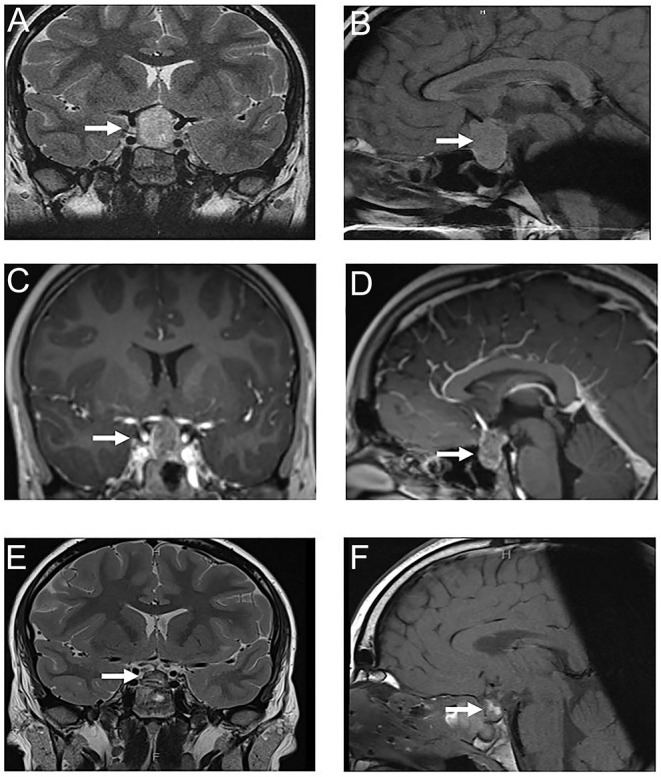

Summary: Paediatric pituitary adenomas are rare in children and adolescents and differ from adults in both clinical presentation and management. We present the case of a 14-year-old female with primary amenorrhoea secondary to a macroprolactinoma, showing a modest radiological and biochemical response to dopamine agonist (DA) therapy. Despite a 10-month duration of increasing DA therapy, initial symptoms of primary amenorrhoea and hyperprolactinaemia persisted, with new symptoms of weight gain, lethargy and low mood. A transsphenoidal resection of the macroprolactinoma was successfully performed, followed by the initiation of additional hormonal therapy. This case explores the unique challenges of treating a macroprolactinoma refractory to medical management in adolescence.

Learning points: Management of macroprolactinomas in childhood and adolescence can bring unique challenges, including a delay in sexual development, often presenting with primary or secondary amenorrhoea in girls.DA therapy is typically the first-line therapy in treating macroprolactinomas; however, resistance in paediatric and adolescent patients is associated with tumour size and initial prolactin levels.Surgical resection should be considered as a second-line therapy for adolescents unable to tolerate high-dose DA therapy or have inadequate response to DA therapy.There are a range of potential surgical complications, including permanent or transient diabetes insipidus, meningitis, cerebrospinal fluid leakage and hypopituitarism.Timely management of macroprolactinomas is important for secondary sex characteristics, bone development and psychological well-being.